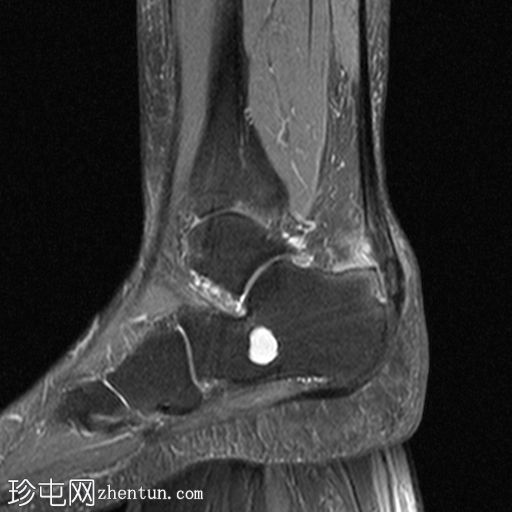

矢状面

PD 脂肪饱和度

跟骨后部骨刺提示 Haglund 畸形。

跟骨隆突后部局部中度骨髓水肿,周围脂肪组织。

其他发现包括跟骨骨刺和跟骨囊肿。